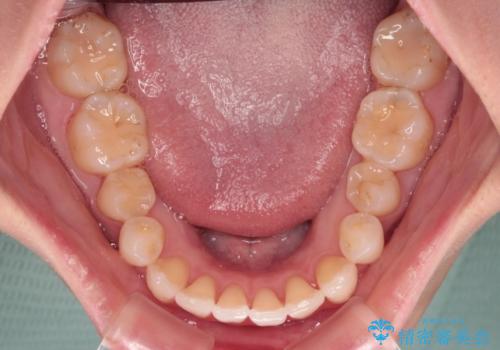

- 上下前歯のデコボコ、特に右上の八重歯を気にして来院された患者様です。

治療後半では悪阻によりマウスピースの装着時間が不十分となることもありましたが、それよりも前にしっかりと装着時間を守って治療を進めることができたため、特に気になるところなく治療を終えることができました。